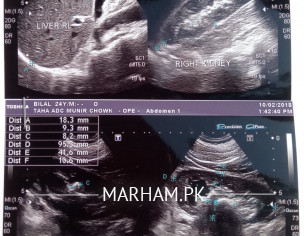

Asking For Self, Male 28, Gujranwala

Sir Left Kidny Me Stone hay laser treatment krwa raha hon 1 saal se lekin stone kbhi kbhi 1, 2 mah baad 1 piece nikalt hay koi aisi medicine jiss se dissolve ho k jaldi nikal jaye